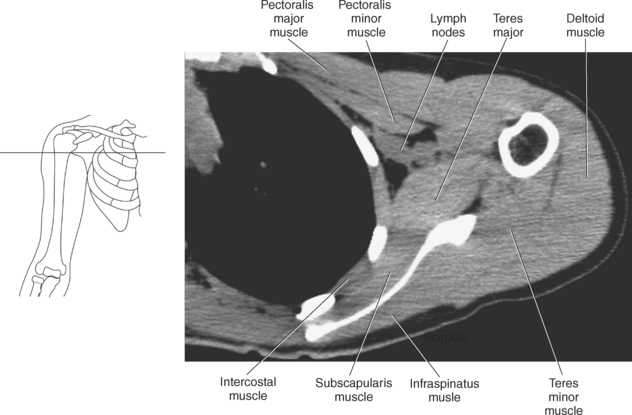

Muscles connecting the upper extremity to the anterior and lateral thoracic walls are demonstrated in Figures 9.34 through 9.47, 9.53, and 9.54 and described in Table 9.3. The pectoralis muscles (major and minor), located on the anterior surface of the chest, primarily aid in the movement of the upper limb (Figure 9.53). The large fan-shaped pectoralis major muscle covers the superior part of the thorax as it spans from the sternum, clavicle, and cartilaginous attachments of the upper six ribs to the lateral aspect or lip of the intertubercular groove of the humerus. Its primary functions are to adduct, medially rotate, flex, and extend the humerus and to assist in forced inspiration. The smaller triangular-shaped pectoralis minor lies beneath the pectoralis major muscle and acts to depress the scapula and assist the serratus anterior muscle in pulling the scapula forward (Figure 9.53). The serratus (sawlike) anterior muscle is visualized on the lateral border of the thorax. It extends from the first rib through eighth rib to the medial border of the scapula. The primary action of the serratus anterior muscle is to protract and stabilize the scapula (Figure 9.54). The subclavius, a small triangular-shaped muscle that spans between the first rib and clavicle, acts to stabilize the clavicle and depress the shoulder (Figure 9.53).